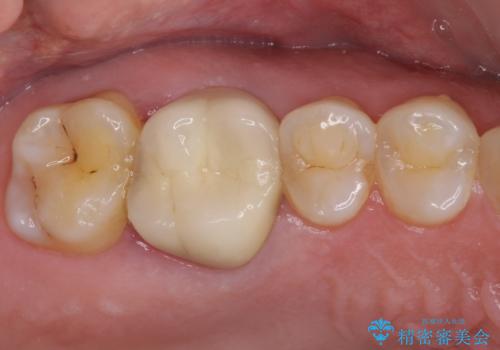

不適合なクラウンのやりかえ

セラミッククラウンによる奥歯のむし歯治療